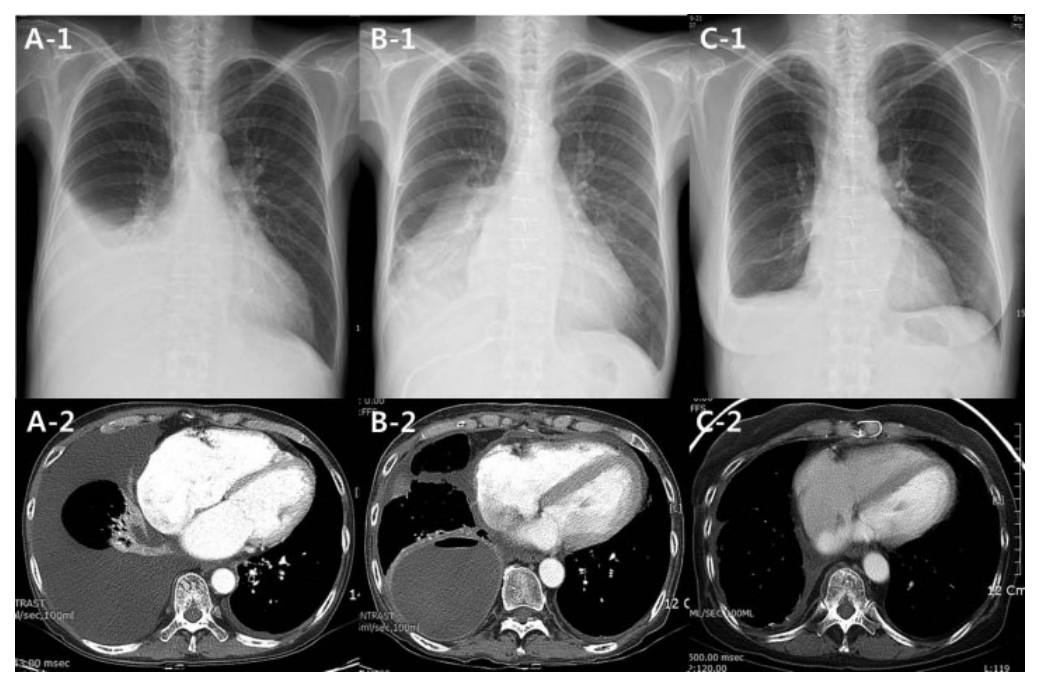

图1. 胸部X光片和计算机断层扫描。

(A) 在心脏移植前,两个影像显示右侧胸腔积液和RLL塌陷。 (B) 心脏移植后,RLL仍然塌陷(B-1)。在RLL中观察到一个大囊性病变(B-2)。 (C) RLL切除术后,所有病变消退,存在极少的胸膜积液。

一位51岁的女性被诊断为严重的限制性心肌病,12年前首次出现临床症状。尽管接受了合适的药物治疗,她的症状仍然逐渐加重。由于反复出现的胸腔积液和腹水,她接受了利尿剂治疗,并进行了间歇性的胸腔穿刺和腹腔穿刺。在一次胸腔穿刺后,压缩的RLL得以扩张,但在随访期间,该部位又再次塌陷(见图1A)。考虑到反复操作可能引发感染和创伤,决定停止胸腔穿刺和腹腔穿刺,并在HT前给予连续3个月的静脉利尿剂治疗。

最终,该患者接受了HT,但其RLL仍然保持塌陷,并继续接受胸腔引流治疗。未能确定限制性心肌病的具体原因,病理检查结果显示仅有间质纤维化,而刚果红染色对淀粉样变性呈阴性。在重新进行CT检查(见图1B)后,通过后外侧胸小切口(15cm切口)进行了VATS下的RLL切除术。术中未发现积液,肺部无法放气,主要是由于存在囊性腔(见图2A)。除了RLL的坏死病灶外,未发现其他特定的病理学变化。此外,还发现了一个带有厚囊壁的大型腔性病变(见图2A-B),腔壁显示出弥漫性纤维化,伴有混合的含铁血黄素巨噬细胞,腔内充满了以中性粒细胞为主的炎症细胞,背景中有纤维素样物质(见图2C)。

在过去四年中,患者未出现任何并发症(见图1C),也没有呼吸困难、感染或运动受限的情况。